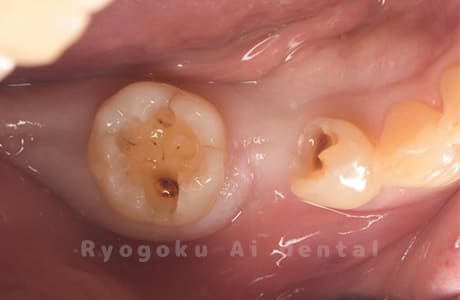

Case08

-

- 原因

- 虫歯

- 治療内容

- セラミックインレー

- 治療費用

- 77,000円

奥歯の黒い点が気になるということで来院された患者さんです。白い詰め物を外したところ、虫歯が中で大きく広がっていたため、患者さんと相談し、セラミックインレーで治療を行いました。

<リスク・副作用>

過度の咬合や衝撃で割れることがあります。